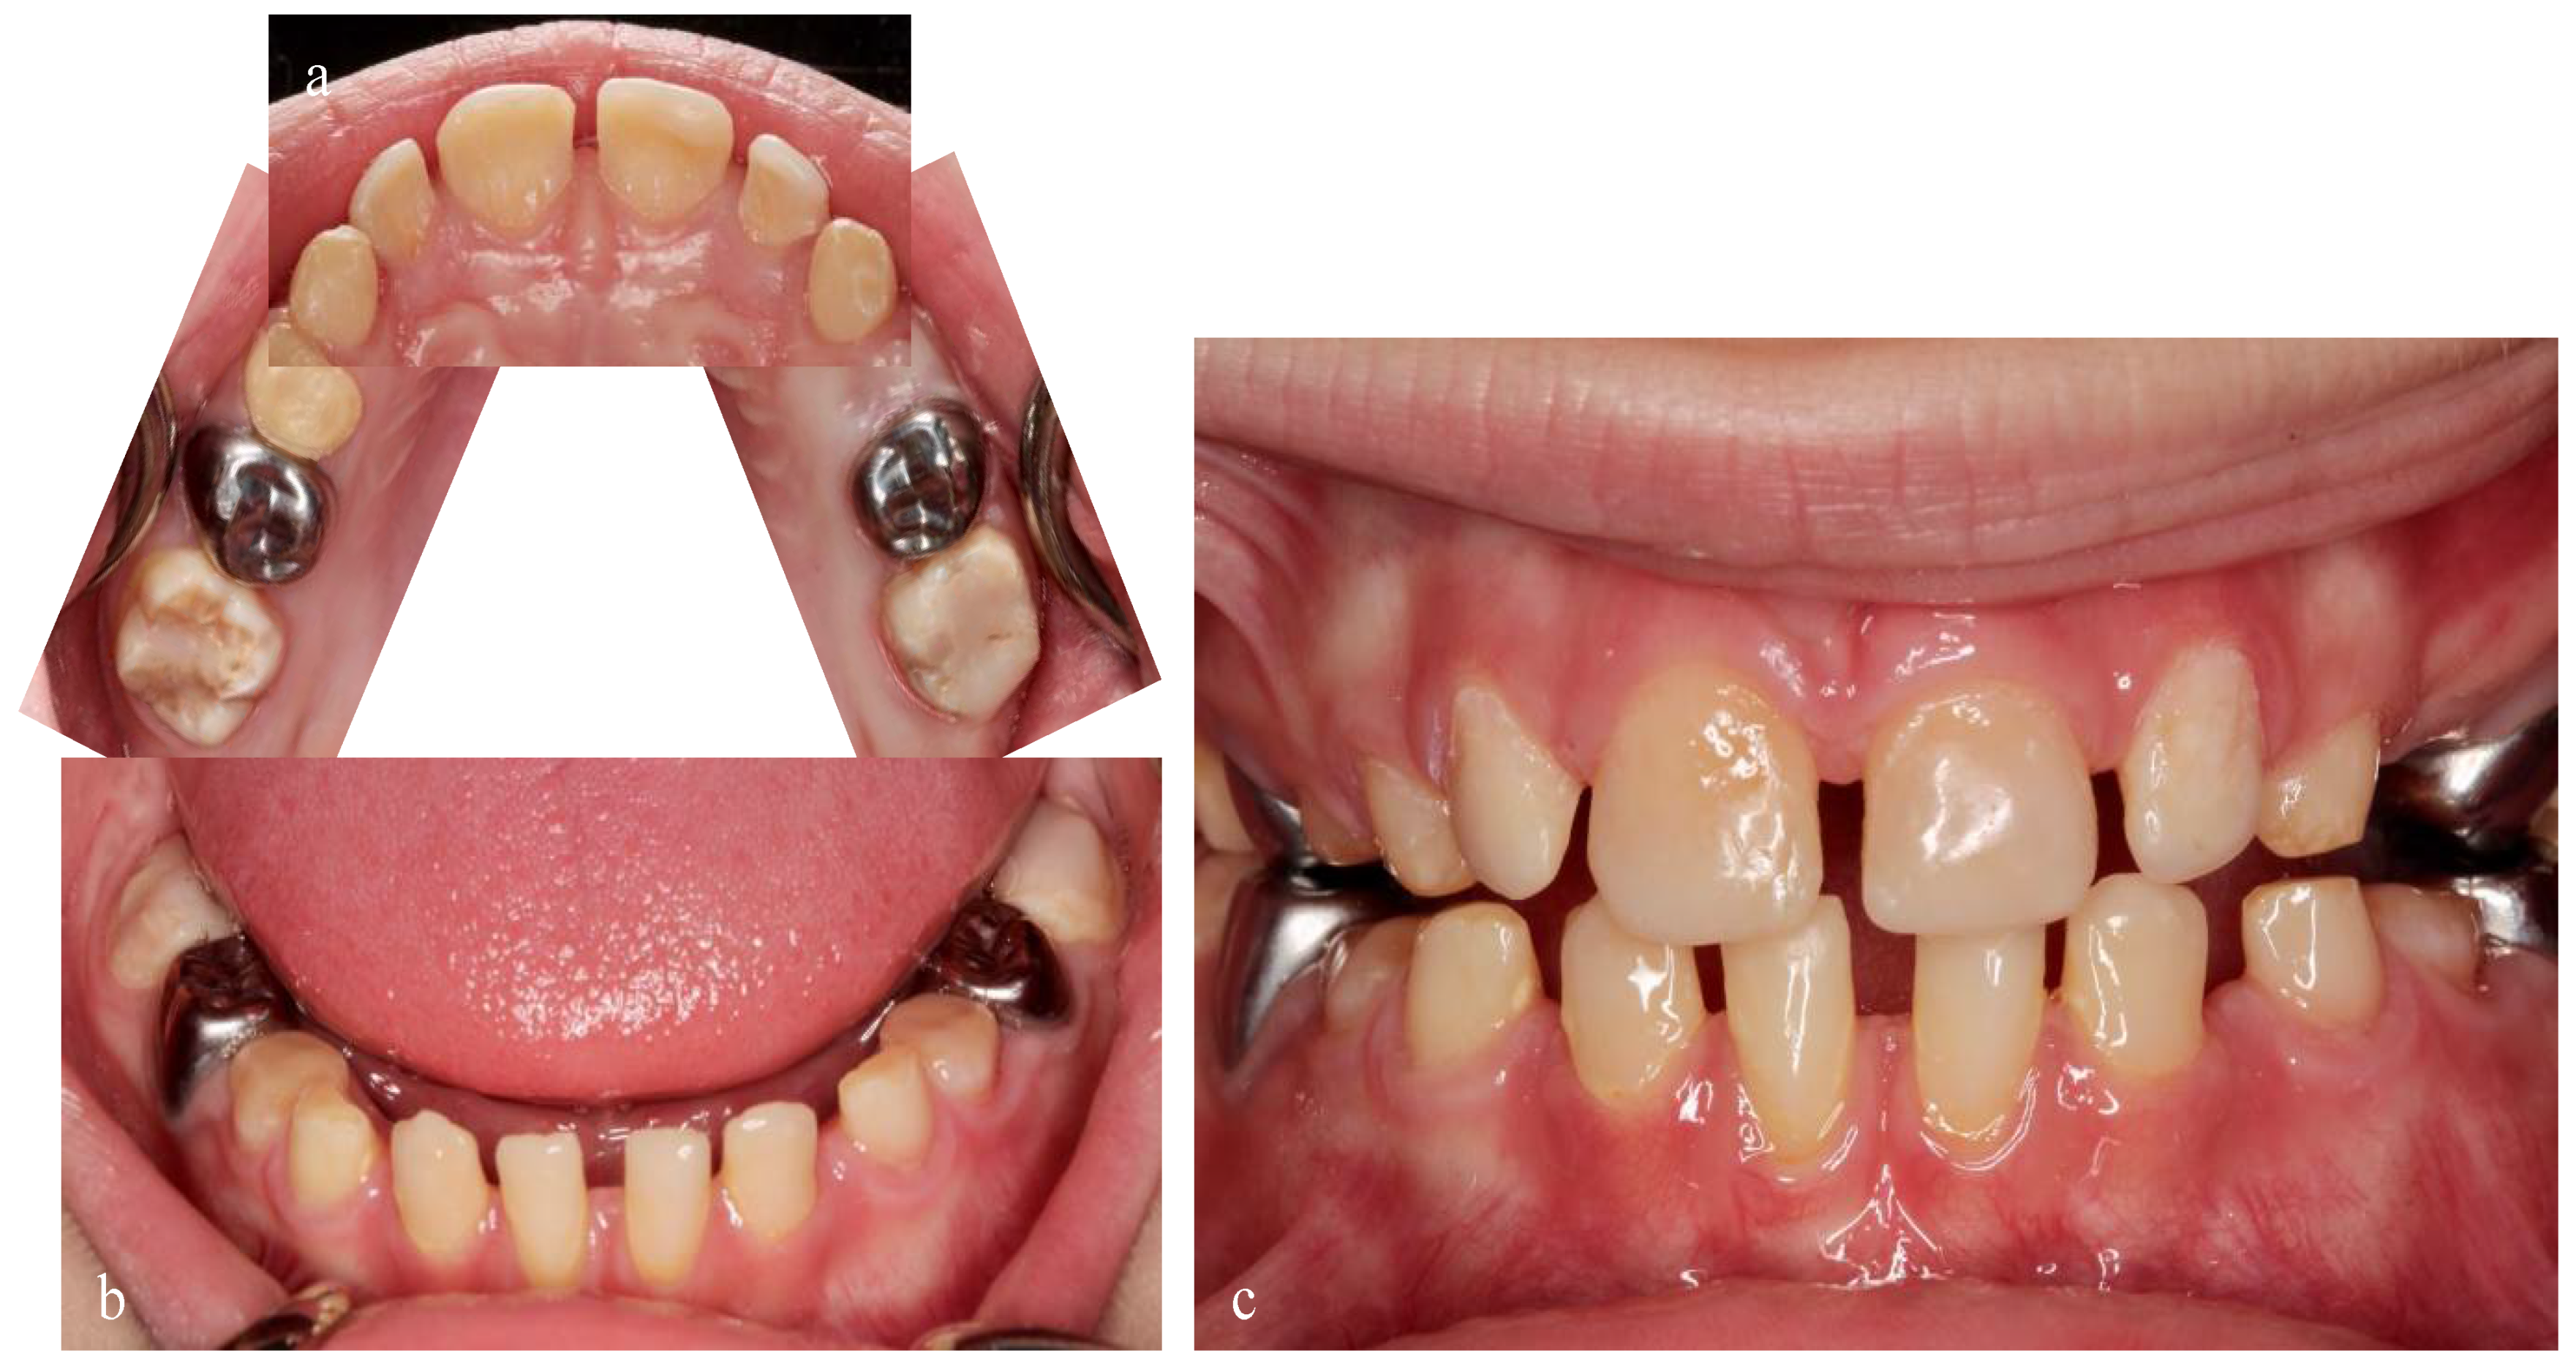

2.1. Case Report 1: Mixed Dentition